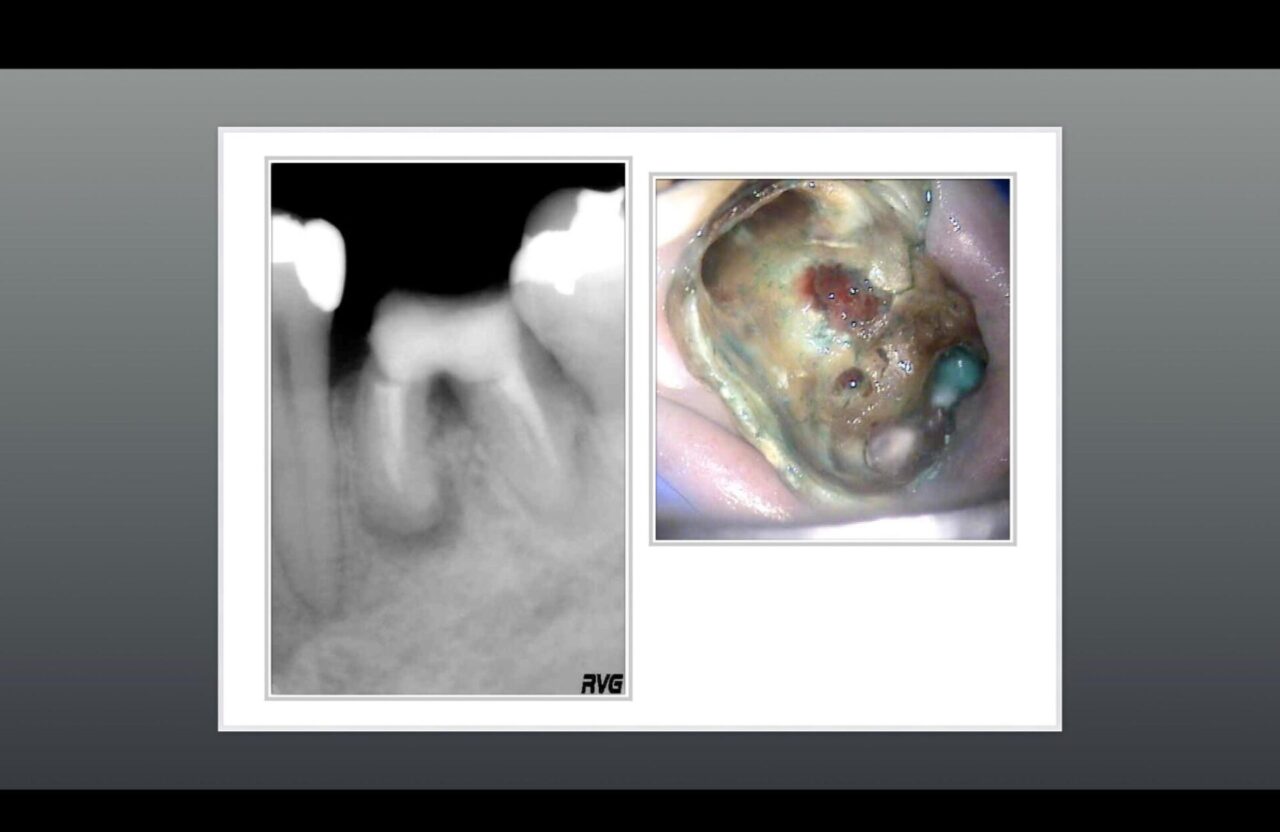

術前と術後のレントゲン➁

術前のレントゲンと術中の口腔内写真、髄床底部に大きなパーフォレーション及びクラックラインが確認できる。

術前のレントゲンと術後のレントゲン、根尖部の骨は再生されており機能させている。

パーフォレーション部の骨も再生されており、適切な修復物が装着され機能している。